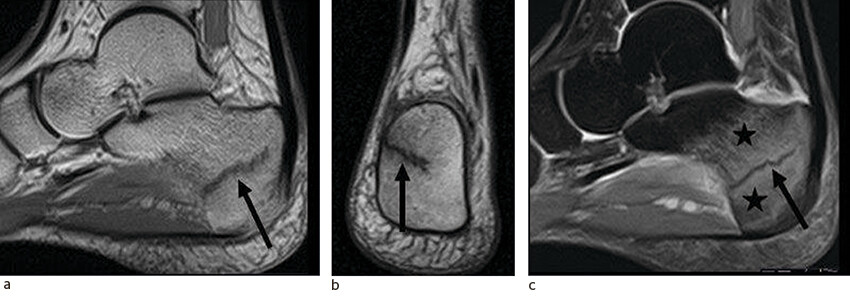

Stressreaksjoner presenterer seg på MR med beinmargsødem som er synlig på T2-vektede sekvenser med fettsuppresjon og STIR-sekvenser (STIR = Short T1 inversion recovery), altså MR-sekvenser der vann lyser hvitt (10, 24) (figur 2). En eventuell frakturlinje vil også være synlig på MR, som et mørkt signal blant annet på protontetthetsvektede sekvenser. Basert på MR-funn er det vanlig å dele slike skader inn i alvorlighetsgrad 1–4, der grad 1–3 betegnes som stressreaksjoner, mens grad 4 er stressfraktur (10). Økt grad er assosiert med lengre rehabiliteringstid (25).